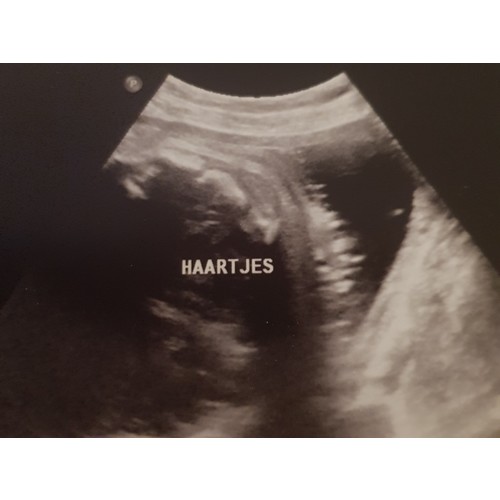

Dit is onze beauty op de echo met haartjes maar is dus nog even afwachten! 30/8 is de uiterekende datum!

Bij ons werd er ook haar gezien op de echo! En hij werd inderdaad geboren met haar! 💙